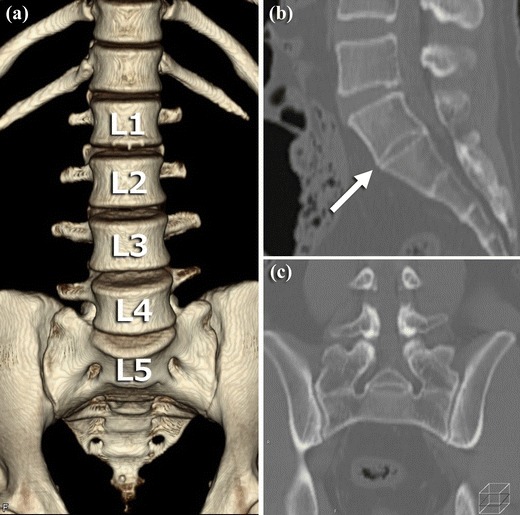

Een CT-scan biedt meer detail van botstructuren dan röntgenonderzoek.

CT kan:

botcontact of fusie nauwkeurig in beeld brengen

asymmetrie beter zichtbaar maken

anatomische details verduidelijken

Beperkingen:

blootstelling aan ioniserende straling

beperkte informatie over weke delen

CT wordt met name ingezet wanneer gedetailleerde botanalyse noodzakelijk is.

Een belangrijk aandachtspunt bij LSTV’s is correcte nummering van de wervelkolom.

Door overgangsvariaties kan:

L5 worden aangezien voor S1

verwarring ontstaan over het exacte niveau

interpretatie van beeldvorming worden bemoeilijkt

Onjuiste nummering kan gevolgen hebben voor verdere diagnostiek en behandeling. Zorgvuldige beoordeling is daarom essentieel.